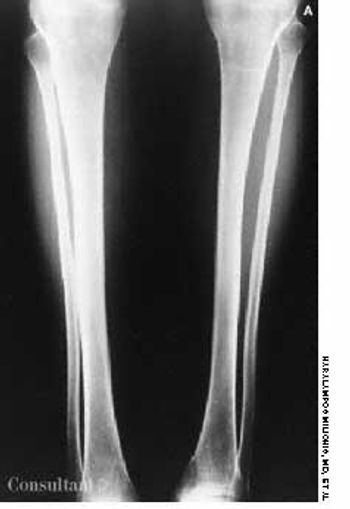

A 2-month history of cough sent a 62-year-old woman for medical evaluation. The patient denied fever, chills, and rigors but reported seeing streaks of blood in her sputum during the past month. The patient had undergone a right nephrectomy 4 years earlier for renal cell carcinoma.

A 72-year-old woman presented for her annual physical examination. She had been treated for tuberculosis 20 years earlier. The patient did not smoke cigarettes; she denied fever, chills, and rigors.